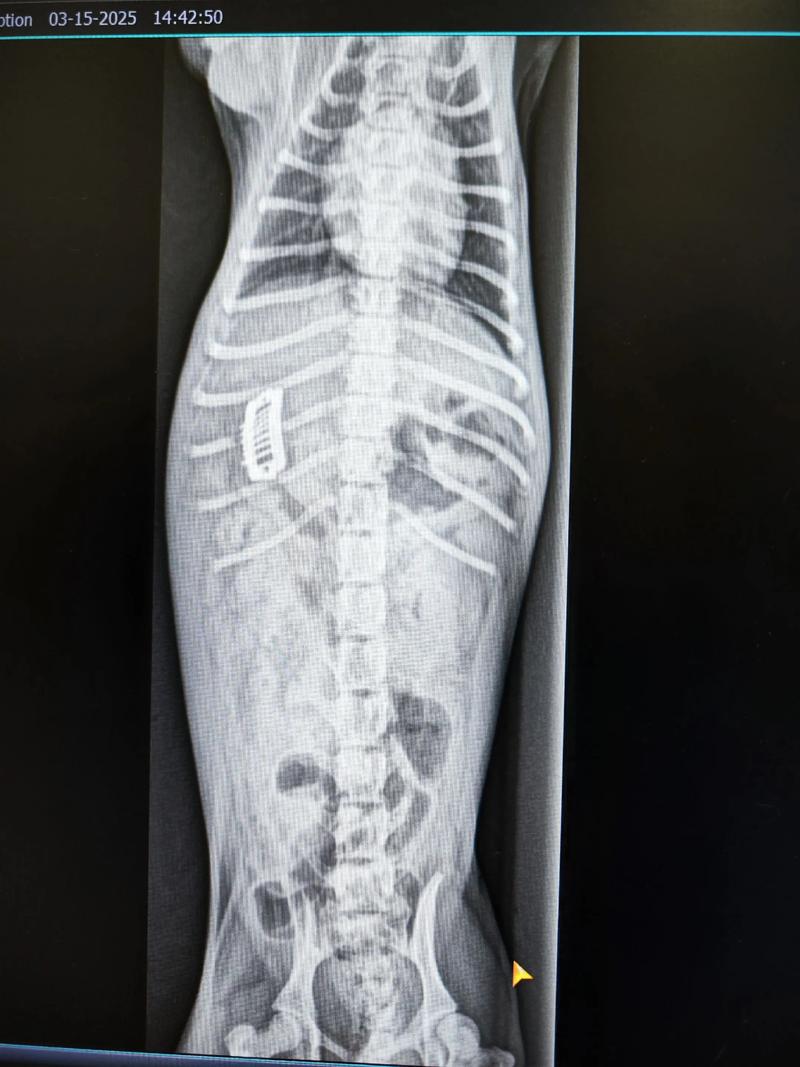

对于胃部或肠道中部的异物,需通过X光观察其移动情况。如果异物能移动,可通过输液维持其状态,等待自然排出。 如果异物位置固定不动,手术移除可能是必要的。 无论采取哪种方法,都应在兽医指导下进行,以确保狗狗的安全和健康。

对于位于胃部或肠道中部的异物,需要通过X光拍摄三张照片来观察其移动情况。如果异物能够移动,可以通过输液维持其状态,并让其自然排出。然而,如果异物位置固定不动,则可能需要进行手术来移除。需要注意的是,无论采取哪种方法,都应在专业兽医的指导下进行。确保狗狗的安全和健康是最重要的。